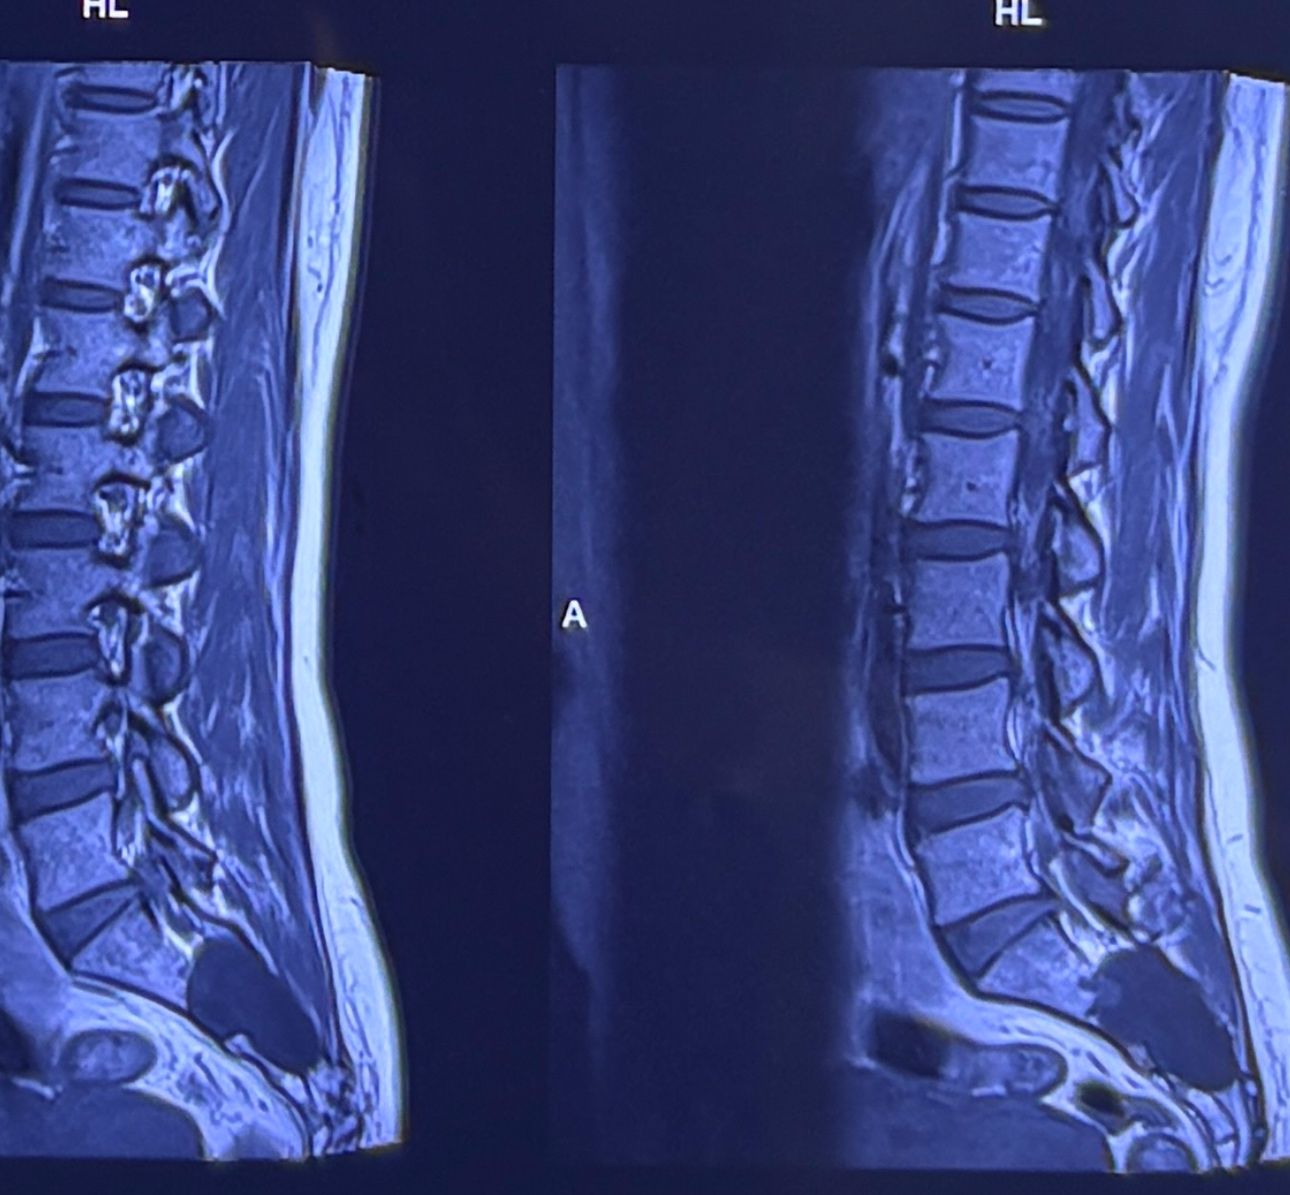

46 years old female patient presented to my clinic yesterday june 1/2025 with LBP and radicular L leg pain for several months which hasn’t responded to physio 2 neurosurgeons have visited her and didn’t suggest any surgery Neurological exam was unremarkable please see her mri/ emg/ncv and her huge tarlov cyst and possible L IVF L4-5 hyperbulge I ordered sacrum mri and ct scan and new emg/ncv and asked her with her sacral Ct scan and MRI first sees another two famous neurosurgeons and see if that large cyst is the reason for her pain if not i can work on her L4-S1 area Do you think her radicular pain can originate from her large cyst in sacrum? Do you consider surgery and removing her sacral cyst?